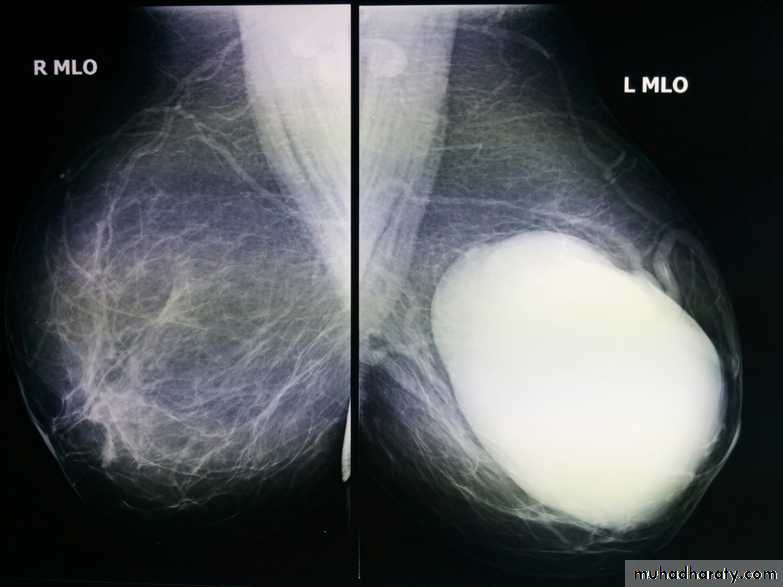

ILC is more often multicentric and bilateral (10-15%). Therefore imaging evaluation of the contralateral breast is crucial. There can be very subtle changes such as progressive shrinkage or enlargement or reduced compressibility of the involved breast. Imaging often underestimates the disease.

The sensitivity of mammography for the detection of ILC reportedly ranges between 55-80% 8. Because of the limitations of mammography in detecting ILC, other modalities, such as sonography and MR imaging, are being used in evaluating clinically suspicious findings and known cancers to assess the extent of disease. ILC are more commonly seen on the craniocaudal (CC), compared to the mediolateral oblique (MLO).